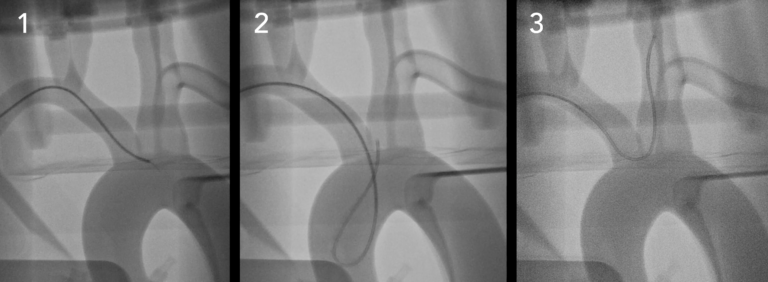

SiM血管造影下的神经径向 轻松模拟各种神经血GJ病状态,例如A脉瘤,中F,AVM等。 在这个平台中,用户可以体验到脉动和真实的触觉反馈。 轻松配置和替换各种特定于患者的模型,以获得一致的结果。 多才多艺 包含: 三、神经血管模拟系统

复制器 四、提供各种可定制硅胶血管:可以根据患者的特定扫描或设计(CT,MRI,3DRA,STL)定制各种血管解剖结构。 这允许用户复制各种程序来训练或开发设备,例如分流器,支架取回器,线圈,支架移植物和其他新型设备。 相合生理合规 |